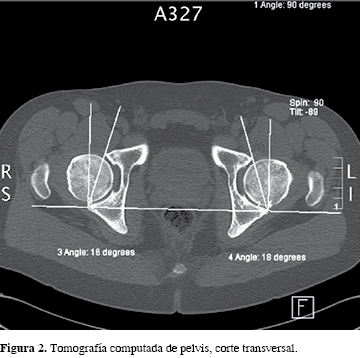

Por ello, se solicitó un estudio imagenológico inicial con radiografía de pelvis anteroposterior (Figura 1) en la que se apreció una osificación alargada sobre la cadera izquierda con base en el hueso ilíaco, en la región de la espina ilíaca anteroinferior. El estudio se amplía con tomografía de pelvis ósea (Figura 2) que mostró osificación sobre cadera izquierda con base en el aspecto posterior del hueso ilíaco, profundo al músculo glúteo menor, ambos cuellos femorales presentaron ángulo alfa aumentado con 68o en derecha y 76o en izquierda7,8 y osificaciones en ambos labrum anterosuperiores mayores en izquierda.

El estudio imagenológico debe ser completado con una tomografía, ya que es más precisa en la determinación anatómica de las deformidades, el cual puede objetivar cuantitativamente signos de pinzamiento como son el ángulo alfa, la versión acetabular y las deformaciones tipo BUMP del cuello femoral,8 además, en el caso de que el pinzamiento sea causado por la EIAI, la tomografía ofrece invaluable información tanto diagnóstica como para la planificación preoperatoria. Está descrito que en radiografías de pelvis AP puede pasar desapercibida una deformidad de EIAI causante de pinzamiento si es que la deformidad está hacia anterior, lo que hace aún más indispensable a la tomografía en caso de sospecha de pinzamiento extraarticular.